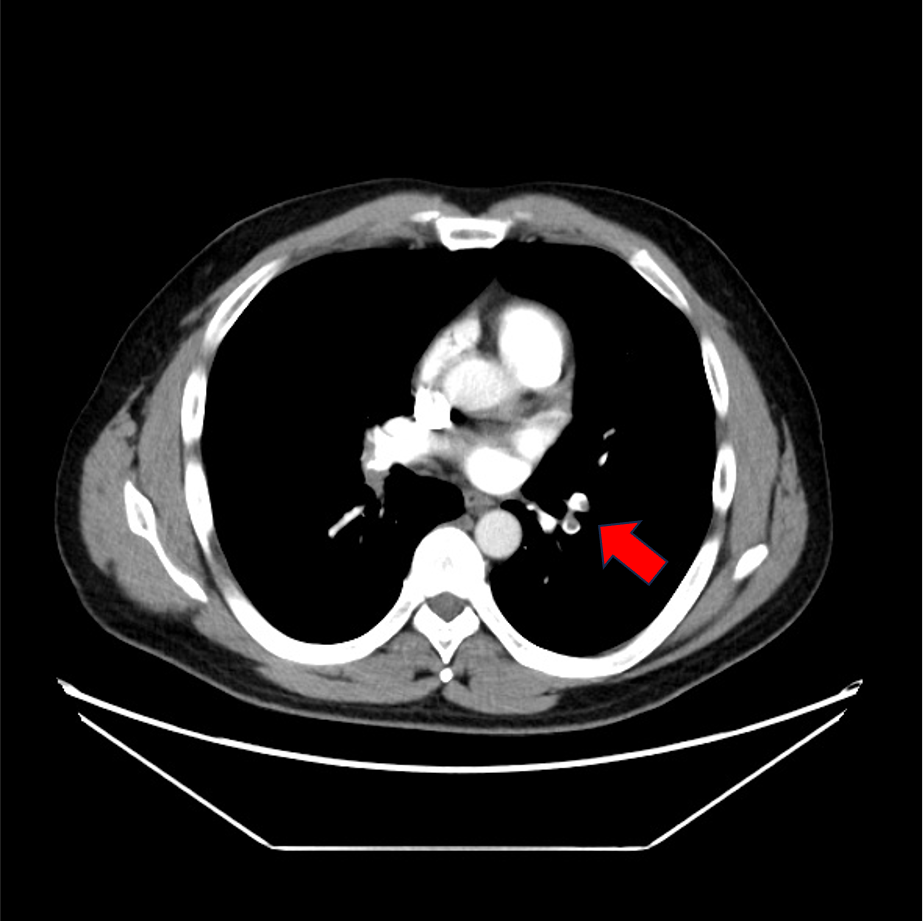

症例は40歳代男性。左下腿の浮腫、疼痛と労作時息切れを認め、血液検査にて血清D-dimerが高値であったため、肺血栓塞栓症の精査目的に造影CTが施行された。両側肺動脈と両側下肢静脈に造影欠損域を認め、それぞれ肺血栓塞栓症、深部静脈血栓症が考えられた。その後、抗凝固療法が施行されて血栓は縮小し、退院となった。

当該疾患の診断における造影CTの役割

肺血栓塞栓症(PE)の診断にはCTが第一選択となる。肺血栓塞栓症の原因の多くは深部静脈血栓症(DVT)であるため、PEが疑われる場合には速やかにDVTの検索も同時に行われることが望ましい。DVTの検査法としては、超音波検査も挙げられるが、胸部の肺動脈相を撮像の後に骨盤部~下肢の静脈相を撮像することで一度に塞栓源の検索が可能となる。これにより速やかな診断と方針決定に寄与することができる。CTではPE、DVTともに血管内の造影欠損を確認することにより診断となる。その他、右心系の負荷評価や他疾患の鑑別も容易になること、低侵襲的に検査できるといった点がCTの利点として挙げられる。一方で、末梢の微小血栓が描出困難な場合や呼吸変動によるアーチファクトで画質低下が生じることがある。また被曝量が比較的多く、臨床情報から適応を判断することが重要である。

CT技術や撮像プロトコル設定について